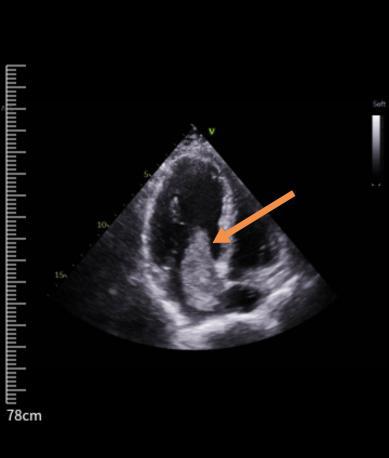

箭头所指是老人的心脏粘液瘤

“患者的左心房粘液瘤有鸡蛋大小,堵在二尖瓣的瓣口,导致血液不能顺畅流入左心室。”李鸿雁副主任医师说,如果再不行手术切除粘液瘤,心脏血流持续受限,且极易造成栓塞,可导致严重后果,甚至危及生命。

两周前,72岁安徽籍李大爷突然感觉胸痛不适,还伴有头晕乏力,休息后症状也没有缓解。于是,家人立即带老人到当地检查,心脏彩超显示是左心房粘液瘤。为进一步诊治,李大爷和家人经亲戚推荐来到中大医院胸心外科门诊就诊。